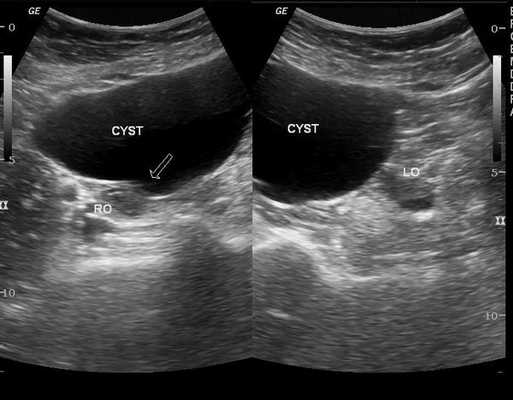

Цель работы - уточнить и усовершенствовать ультразвуковые дифференциально-диагностические критерии жидкостных объемных образований органов мошонки, а именно: ретенционных кист, сперматоцеле и гидроцеле.

Кисты яичка (n = 8) клинически не определялись и были случайной находкой при УЗИ. Во всех случаях кисты имели вид анэхогенного округлого с четкими ровными контурами (но без определяемой стенки) образования с дистальным звукоусилением, расположенного внутри яичка под белочной оболочкой или в области средостения (рис. 1, 2). Эхотекстура паренхимы яичка рядом с кистой была обычной, за исключением одного случая тубулоэктазии сети яичка (ТЭСЯ), которая визуализировалась как образование в области средостения яичка (рис. 3), состоящее из множества мелких округлых или трубчатых анэхогенных структур (симптом "грейпфрута" [5]).